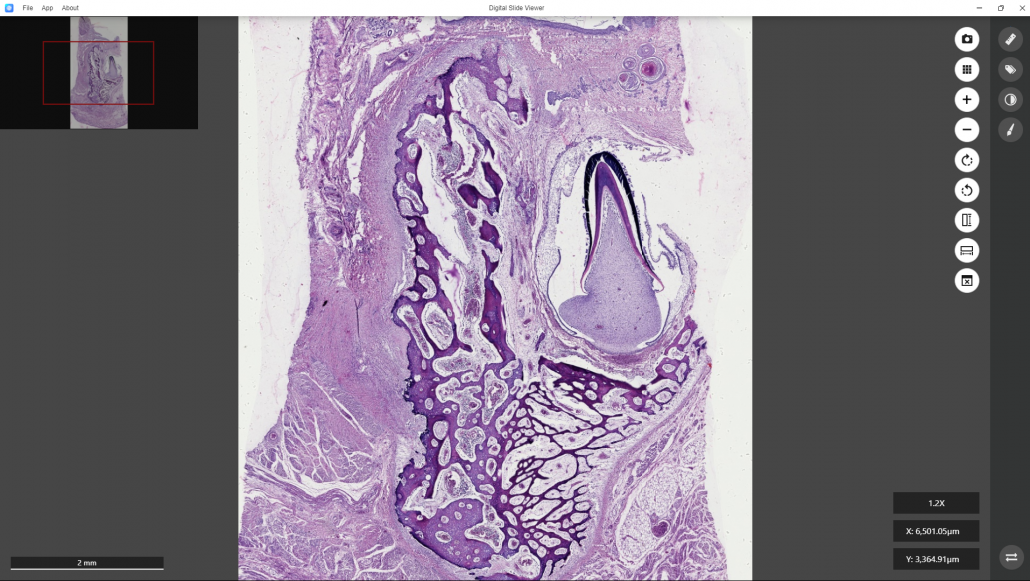

The whole section image of OH0014(2)will be brought into the window of the DS Viewer.

This is a digitized image of a sectioned developing tooth enveloped by periodontal tissue. The tooth erupt toward the right.

By clicking the “Rotate Toward Left” or “Rotate Toward Right” command at the right bar of the software, the image can be rotated to showthe tooth eruption toward the top. A small window at the top left corner shows the location of the enlarged image in the entire section.